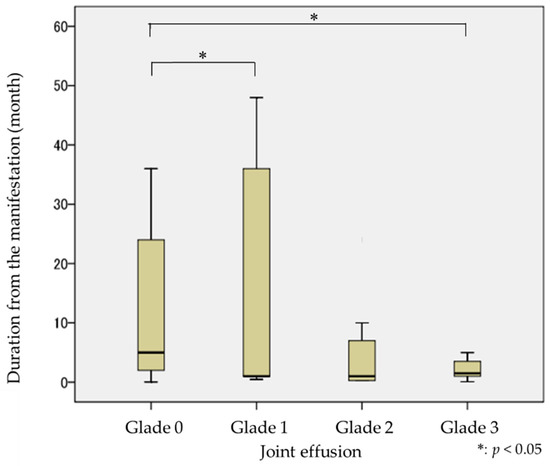

The difference in synovial fluid in joint effusion, according to the duration of manifestation, is shown in Figure 3. The median value for manifestation duration in Grade 0 (no fluid) was four months; in Grade 1 (fluid with punctiform or filamentous), it was one month; in Grade 2 (fluid with cingulate), it was three months; and in Grade 3 (fluid with plenitude), it was two months. There were statistically significant differences between Grade 0 and Grade 1 (p < 0.05), and Grade 0 and Grade 3 (p < 0.05), concerning the duration of manifestation. The amount of synovial fluid in joint effusion observed in MR images was greater for shorter manifestation durations.

Figure 3.

Amount of synovial fluid on joint effusion by the duration from the manifestation.

The amount of synovial fluid in joint effusion was investigated as the hyperintense area of the superior or inferior articular cavities in T2-emphasized MR images, and the amount of synovial fluid in joint effusion was classified from no fluid (Grade 0) to fluid with plenitude (Grade 3). The differences in the grade of joint effusion vs. manifestation duration were analyzed to clarify the timing of joint effusion appearance. The results indicated that the duration of manifestation was longest in TMJs with no fluid on the superior or inferior articular cavities compared to that with fluid with punctiform or filamentous and fluid with plenitude on the superior or inferior articular cavities. Namely, the amount of synovial fluid in joint effusion differed with manifestation duration. The amount of synovial fluid in joint effusion was larger when the manifestation duration was short. This result suggested that joint effusion reflects the inflammation of the articular cavities in the early stages.